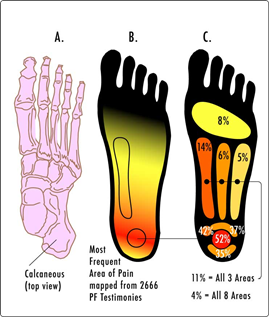

Разрывы могут случиться в разных участках плантарной фасции, поэтому боли при фасците могут быть в разных участках стопы, но чаще всего в области пятки.

Пока стопа отдыхает без нагрузки в месте разрыва или разрывов начинают формироваться нежные рубцы, которые легко рвутся при интенсивной нагрузке. Поэтому мы и испытываем боли после ночного отдыха или после того, как долго посидим, а потом резко встанем.